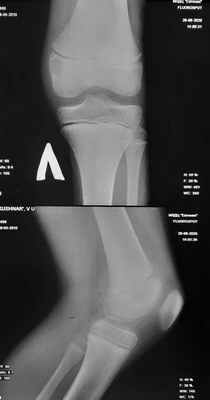

Остеобластокластома (гигантоклеточная опухоль) возникает в молодом возрасте (у лиц моложе 30 лет), поражает как эпифиз, так и метафиз длинных трубчатых костей • Патоморфология: наряду с одноядерными овальными клетками типа остеобластов обнаруживают многоядерные крупные гигантские клетки типа остеокластов • Формы: литическая, активно-кистозная и пассивно-кистозная • Клиническая картина: боль в области поражения, иногда — гиперемия кожи, деформация кости, возможны патологические переломы • Рентгенологическое исследование. Опухоль имеет вид овального очага просветления. Важным рентгенологическим признаком всех форм остеобластокластомы, отличающим её от туберкулёзных поражений кости, служит отсутствие остеопороза • Дифференциальная диагностика: исследует исключить дисплазии (хондрома, хондробластома, фиброзная дисплазия и др.) • Лечение остеобластокластом хирургическое. Щадящая резекция кости с удалением опухоли и одномоментной костной пластикой (ауто-, гомотрансплантаты либо замещение метилметакрилом) — метод выбора. При поражении опухолью позвоночника применяют лучевую терапию.

Доброкачественные гигантоклеточные опухоли кости при визуализации проявляются как экспансивное литическое поражение. При визуальных исследованиях обнаруживается склеротический ободок –граница между опухолью и нормальным губчатым веществом кости. Необходимо выполнение биопсии. Поскольку гигантоклеточная опухоль кости может метастазировать в легкие, на начальной стадии проводится КТ грудной клетки.